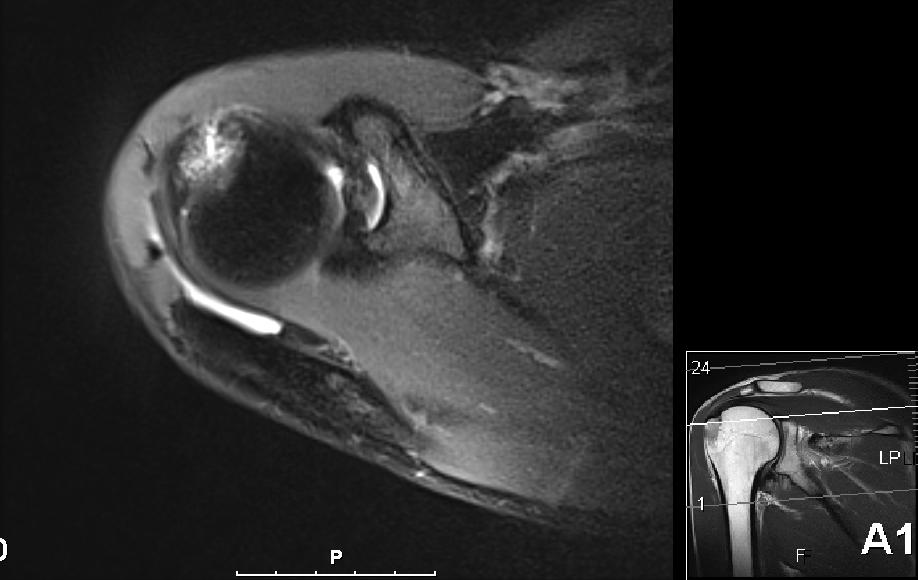

Heldigvis har det vært fremgang hele veien og det har blitt bedre hver dag. For 2 uker siden hadde jeg min første ”normale” svømmeøkt der jeg svømte crawl med begge armene. Det var noe sporadisk smerter forbundet med det, men veldig lite og 4000 meter med svømmeføtter (for å avlaste armene litt) gikk helt greit. Etter det har det blitt flere gode svømmeøkter der det har vært stor fremgang i den forferdelig rustne svømmeformen. Bare for å få bekreftet min mistanke om at det kun er noe mindre betennelse igjen og at det ikke var noe annet galt så fikk jeg dratt innom Aleris Oslo for en MR-undersøkelse. Dette var noe min kiropraktor Kristian og fysioterapeut Jørn Erik hos Klinikk for Alle ønsket hele veien men med ukependling til Stavanger og en veldig tettpakket plan før og etter Ironman Sør-Afrika så tok var drøye 5 uker etterpå det første jeg fikk til.

I forrige uke kom uansett svaret og resultatet var ikke akkurat helt som forventet. Nå var det riktig nok noe betennelse (aka bursitt) i skuldra som forventet men det var også et brudd i kanten på skuldra, såkalt tuberculum majos fracture på 2 x 2 cm. Så Kristian og Jørn Erik var rimelig overrasket over at jeg meldt tilbake at svømmingen gikk så bra.

Nå er det bare 6 dager til Ironman 70.3 Mallorca, og som alltid så ønsker jeg selvsagt å delta, men forstår at det kanskje ikke er det mest fornuftige. Om noen av dere har erfaringer eller gode råd/tips så tas de i mot med stor takk! Nå forstår jeg at radiolog er et eget yrke og tolking av MR-bilder krever mye erfaring og kunnskap, men jeg syntes ikke det ser såååå ille ut egentlig.

Skulderbilde